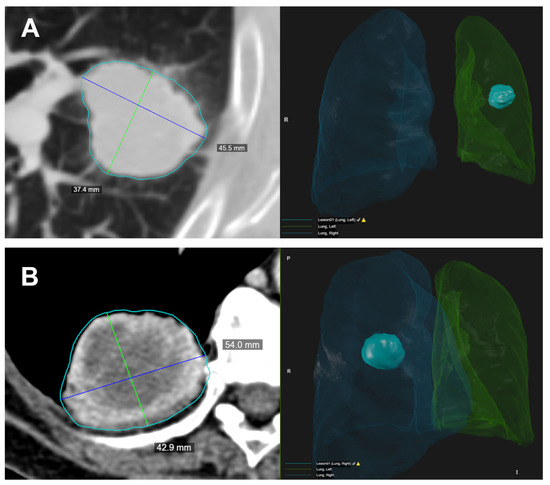

2.4. CT Post-Processing with Radiomic Precision Metrics (RPM™) Tool